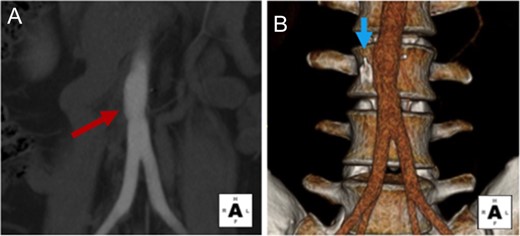

A 25-year-old man presented to attention with progressive intermittent abdominal and back pains. The patient had a history of antiphospholipid syndrome, who 10 years ago developed a recurrent pulmonary embolus (PE) and lower extremity deep venous thrombosis (DVT) despite therapeutic anticoagulation. He was treated with daily Rivaroxaban therapy and a retrievable Gunther Tulip (Cook, Inc., Indianapolis, IN) IVC filter was placed in his infrarenal IVC. At the time of presentation, the patient had an unremarkable exam, but a CTA demonstrated a segmentally occluded distal infrarenal IVC (Fig. 1A). The IVC filter limbs were protruding out of the small atretic IVC, and extending into the infrarenal aorta, L3 vertebral body and right psoas muscle (Fig. 1). The IVC filter limb protruding into the aorta was also piercing the aortic backwall, and was a nidus for partial thrombosis and stenosis of the aortic lumen (Fig. 1B and C). Given the patient’s symptoms and severity of filter limb injury into the aorta, the patient was offered an open explantation of the IVC filter and repair of the infrarenal aorta (Fig. 2).

Preoperative CTA demonstrates Gunther Tulip IVC filter perforation of the infrarenal aorta, lumbar spine and psoas muscle. (A) IVC filter in occluded atretic appearing infrarenal IVC (white arrow). IVC filter legs are protruding out of the IVC wall, embedding into the adjacent right psoas muscle (yellow arrow), and adjacent infrarenal aorta (red arrow). (B) Coronal view demonstrates partial obstruction of the aortic lumen at the tip of the perforating IVC filter leg (red arrow). (C and D) Transverse cross-sectional views demonstrates protrusion of filter leg in aorta and partial obstruction of aortic lumen (red arrows), as well as embedding of one of the filter legs into the L3 vertebral body (blue arrows). (E–G) Three dimensional reconstructions also demonstrate protrusion of the IVC filter legs into the aorta (red arrows), and lumbar spine (blue arrows).